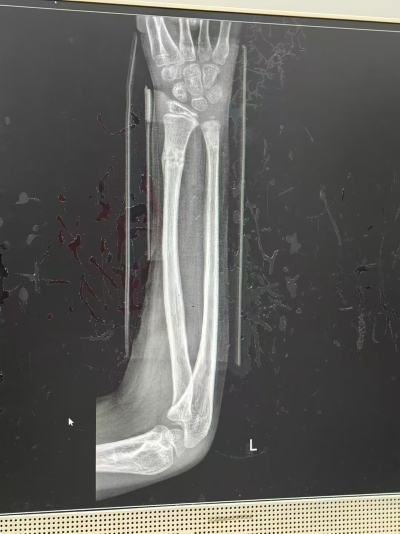

近日,华侨中医院迎来了一位12岁前臂骨折的患者(双骨折),第五掌骨(掌指关节端骨折,翻转移位,西医院告知必须手术,费用最少10多万铢,西医院已安排手术治疗,患者要求保守治疗,之后在网上看到华侨中医院有专业医生的介绍,经过骨伤推拿科资深中医师李汉成的精心治疗,患者恢复如初(达到解剖复位),患者非常满意,为此特别送来了锦旗,表达感激之情。

患者在一次意外事故中不慎摔伤,导致前臂骨折。经常规的西医治疗后,虽已固定,但由于伤势较重且复原缓慢,患者的前臂活动仍受到严重限制,疼痛不减。由于长期的疼痛与功能障碍,患者在治疗过程中感到无比困惑和焦虑。

在初次会诊时,李汉成医生仔细询问了患者的病史,并结合中医的脉诊与舌诊,全面了解了患者的整体健康状况。李医生通过中医推拿的方式,对骨折部位进行治疗。通过推拿手法疏通筋脉,促进骨折愈合。

患者在接受李医生治疗的几天后,明显感到疼痛减轻,前臂活动逐渐恢复。随着治疗的继续,骨折部位愈合进展迅速,患者的日常活动逐渐恢复正常。经过一段时间的调养,患者终于康复,重获健康。